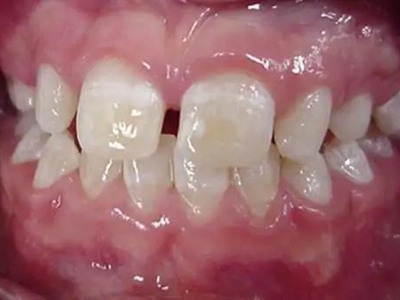

牙齿

白点

牙釉质发育不全牙齿上有白点图

牙釉质发育不全病情较轻者,只表现为牙齿上有白点,形状不规则,造成牙齿的透明度下降,但牙齿形态依旧完整,也不影响进食。